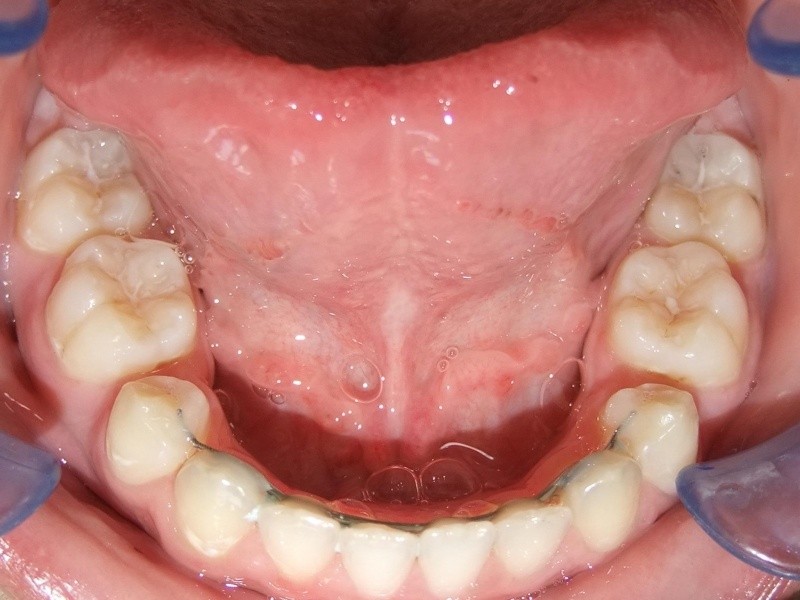

Voor behandeling

Na behandeling